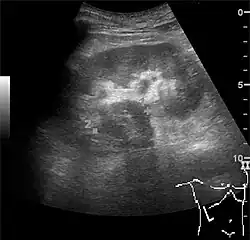

Complex cysts can have membranes dividing the fluid-filled center with internal echoes, calcifications or irregular thickened walls. The complex cyst can be further evaluated with Doppler US, and for Bosniak classification and follow-up of complex cysts, either contrast-enhanced ultrasound (CEUS) or contrast CT is used (Figure 6). The Bosniak classification is divided into four groups going from I, corresponding to a simple cyst, to IV, corresponding to a cyst with solid parts and an 85–100% risk of malignancy.[1] In polycystic kidney disease, multiple cysts of varying size in close contact with each other are seen filling virtually the entire renal region. In advanced stages of this disease, the kidneys are enlarged with a lack of corticomedullary differentiation (Figure 7).[1]

Figure 7. Advanced polycystic kidney disease with multiple cysts.[1]